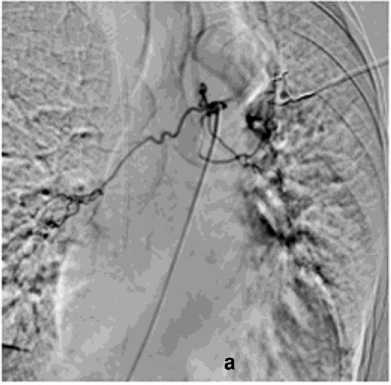

Рисунок 9. Аортография у пациента после трансплантации лёгких, ЛК 3Б: а – аорто-бронхиальный свищ с поступлением контраста в левый главный бронх; б – эндопротезирование нисходящего отдела аорты протезом Ankura TAA2622B160 – без признаков экстравазации

Figure 9. Aortography in a patient after lung transplantation, PH grade 3B: a – aortobronchial fistula with contrast extravasation into the left main bronchus; б – endovascular repair of the descending aorta with Ankura TAA2622B160 stent graft – no signs of extravasation

В общей сложности погибло два пациента с аорто-бронхиальными свищами и ЛК3Б. Причиной кровотечения в одном случае у пациентки 86 лет явилось расслоение грудного отдела аорты с прорывом в бронх, в другом – у пациентки 31 года после трансплантации лёгких, стентирования стриктуры левого долевого бронха вызвало в последующим пролежень аорты. После эпизода массивного ЛК пациентам проведён полный комплекс гемостаза, включая стентирование аорты (1), санацию трахеобронхиального дерева (2), бронхоблокацию, на фоне ИВЛ (2) (рис. 9, б).

Первым этапом в процессе диагностики бронхоскопии через фибробронхоскоп выполняли промывание трахеи холодным физиологическим раствором, инъекции адреналина (рис. 5). При наличии и доступности определённого источника кровотечения использована электрокоагуляция с ис- сечением опухоли бронха 4 (2,7%), бужирование и стентирование бронха 11 (7,3%). При интенсивном кровотечении в 13 (8,7%) случаях выполняли брон-хоблокацию. Удаление блокатора осуществляли на 5–8 сутки. В одном случае бронхоблокация сочеталась со стентированием аорты. Проведённый анализ ангиограмм позволил выявить косвенные признаки ЛК. В большинстве случаев наблюдалось усиление кровоснабжения зоны поражения независимо от выявленной патологии (рис. 6, а). Локализация сосудистых изменений соответствовала данным, полученным при таких диагностических методах как ФБС и КТ. Эти ангиографические признаки не имеют прямого отношения к ЛК, но достаточно полно характеризуют его причину в силу специфичности семиотики различных лёгочных заболеваний. Прямые признаки экстравазации мы наблюдали в одном случае при наличии аортобронхиального свища (рис. 9, а).